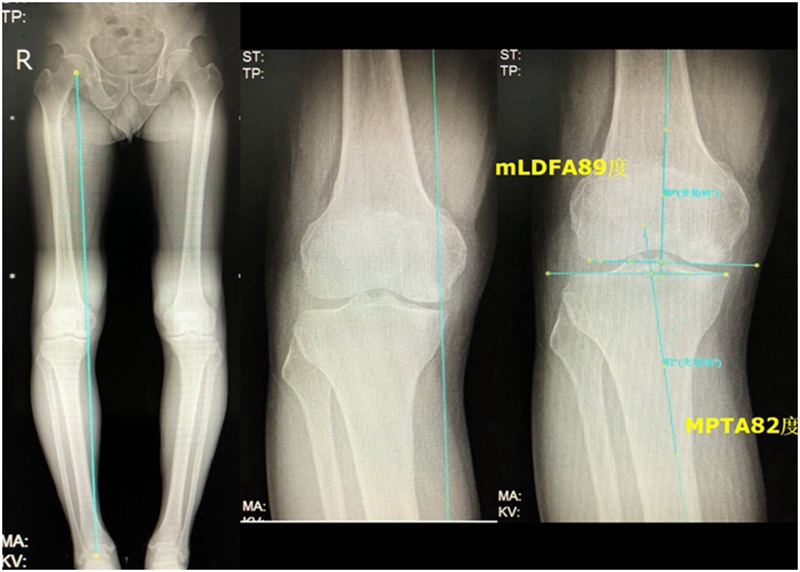

关于SONK与下肢力线的关系,一项研究结果显示SONK组MPTA畸形比OA组更大,高达约1.5°,SONK组JLCA也显著高于OA组。

提示胫骨近端内翻畸形和膝关节松弛,有助于诱发SONK,SONK骨软骨病变的大小受胫骨近端内翻畸形的影响。临床中MPTA小于 84°且伴有急性膝关节疼痛应尽快MRI检查。

膝内翻 内侧半月板根部撕裂

应力源性理论

病例1:男,64岁,主诉左膝关节内侧疼痛6年余。MR提示骨坏死区占比为33.28%,矢状位病变区域前后径为26.42mm,半月板相对突出百分比(RPE)31.78%,同时存在胫骨侧来源的下肢内翻畸形(MPTA83°),关节线会聚角2°。